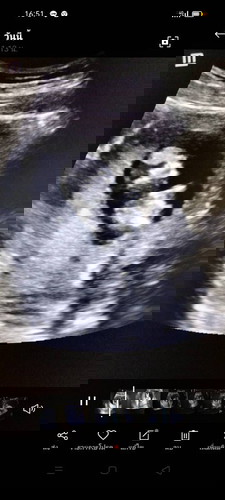

13สัปดาห์3วัน

ท้องแรกค่ะบ้านนี้ดิ้นเก่งมากค่ะ มาโชว์น้องๆกันน่อยจ้าแม่ๆๆ

นี่ก็ดิ้นตอนซาวด์ตั้งแต่ 10w ค่ะ ดื้อตั้งแต่อายุครรภ์ยังน้อยๆเลย จนตอนนี้ 26w5d ก็ยังคึกเหมือนเดิม ถีบทีพุงสะเทือนไปหมด 😂

ดิ้นในครรภ์ตอนซาวด์เหมือนบ้านนี้เลยค่ะ คุณหมอบอกให้โชว์ก็ดุ๊กดิ๊กใหญ่ ปัจจุบัน 21 week 3 day ดิ้นเก่งมาก 😊